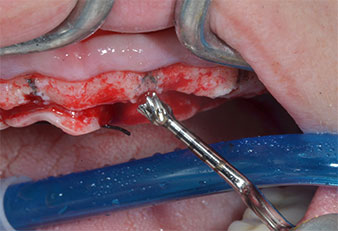

A flame-shaped, diamond-coated piezoelectric instrument (Piezomed I1) was used to mark the implant positions and to perform pilot preparation (Fig. 3). Care was taken to use an up and down movement, with reduced power, full irrigation and low pressure (below 300 g). Next a pilot instrument (Piezomed I2A/I2P) was applied for the initial 2 mm diameter enlargement of the implant sites (Fig. 4), followed by a 3 mm insert (Fig. 5).

In the present case the Z25P and Z35P instruments were not used due to the relatively soft posterior bone, which was easily managed with the I3A/I3P.